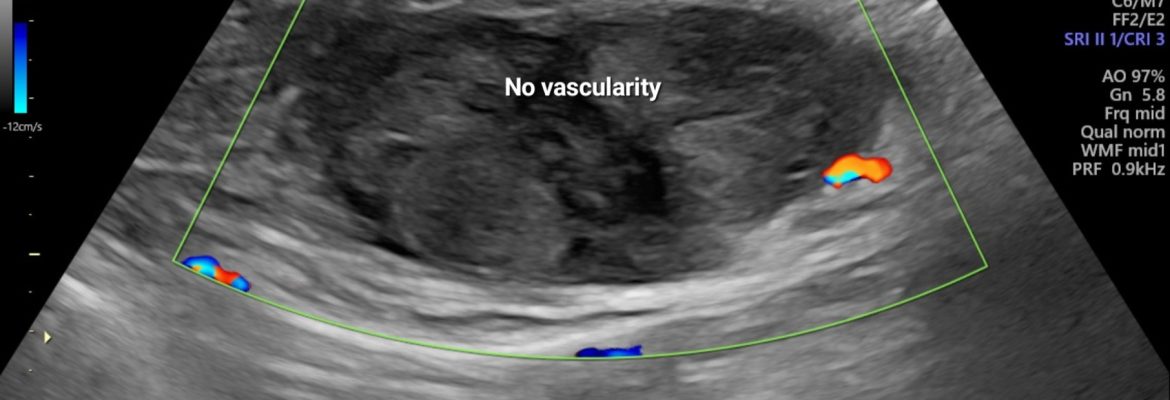

On B mode ultrasound:

There is well defined heterogenous predominantly hyperechoic lesion/ area is seen involving the left rectus abdominis muscle. No intra- abdominal extension is noted.

On Color Doppler examination: No vascularity noted.

So, the diagnosis of acute rectus abdominis muscle hematoma is given.

Doppler Ultrasound Features:

• No significant internal vascularity (distinguishes hematoma from tumors).